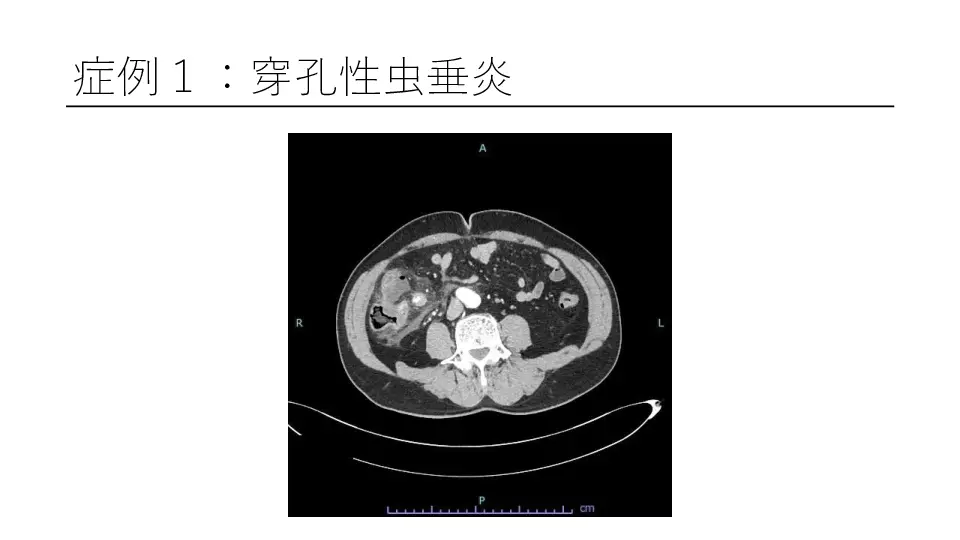

「反跳痛があります」と記載された紹介患者や、研修医からコンサルトにおいて、意外と腹膜炎ではないパターンが散見されます。 若手外科医だからこそ語れる腹膜炎のはなしを聞いてください。 #腹膜炎,#反跳痛の診かた,#コンサルト,

外科医目線の腹膜炎 ~これが腹膜刺激兆候です~